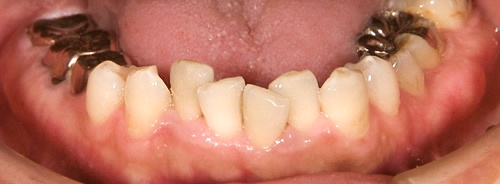

ガタガタ歯並び

大人になっても気になってしまうガタガタ歯並び。治せるなら治したい。

でも。。。その一歩を踏み出せない方が数多くいらっしゃいます。

大人になってから矯正器具が見えるのが恥ずかしいという方も沢山いらっしゃいます。

当院では透明なマウスピース矯正、ワイヤー矯正、セラミックによる審美治療などがあります。マウスピース矯正は、周りの人にほとんど気付かれません。

歯の矯正やセラミックによる治療には見た目ももちろんのこと他にも沢山のメリットがあります。

治療後

治療前